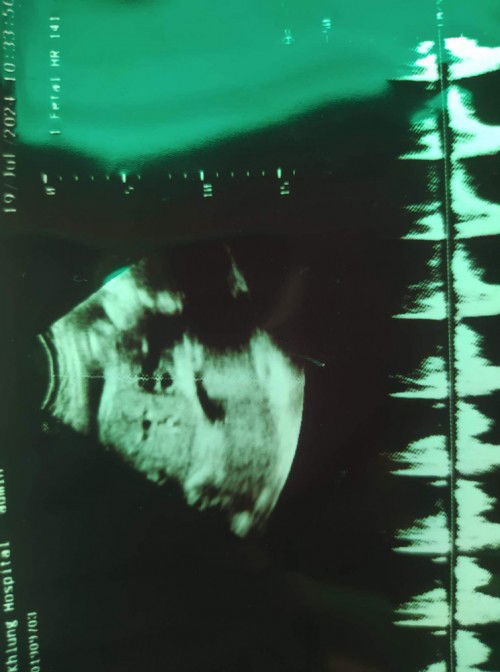

สอบถามแม่ๆหน่อยค่ะ ใครพอดูออกบ้างคะ อยากทราบค่ะ หมอบอกแค่ลูกปกติ แต่ไม่ได้บอกว่าส่วนไหนเป็นอะไรบ้าง #28สัปดาห์ #ขอบคุณล่วงหน้านะคะ #ขอบคุณสำหรับคำตอบค่ะ #ท้องแรกค่ะ